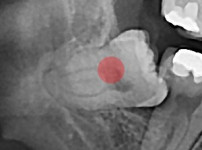

완전 매복 사랑니

조회

910

작성일

25-11-28